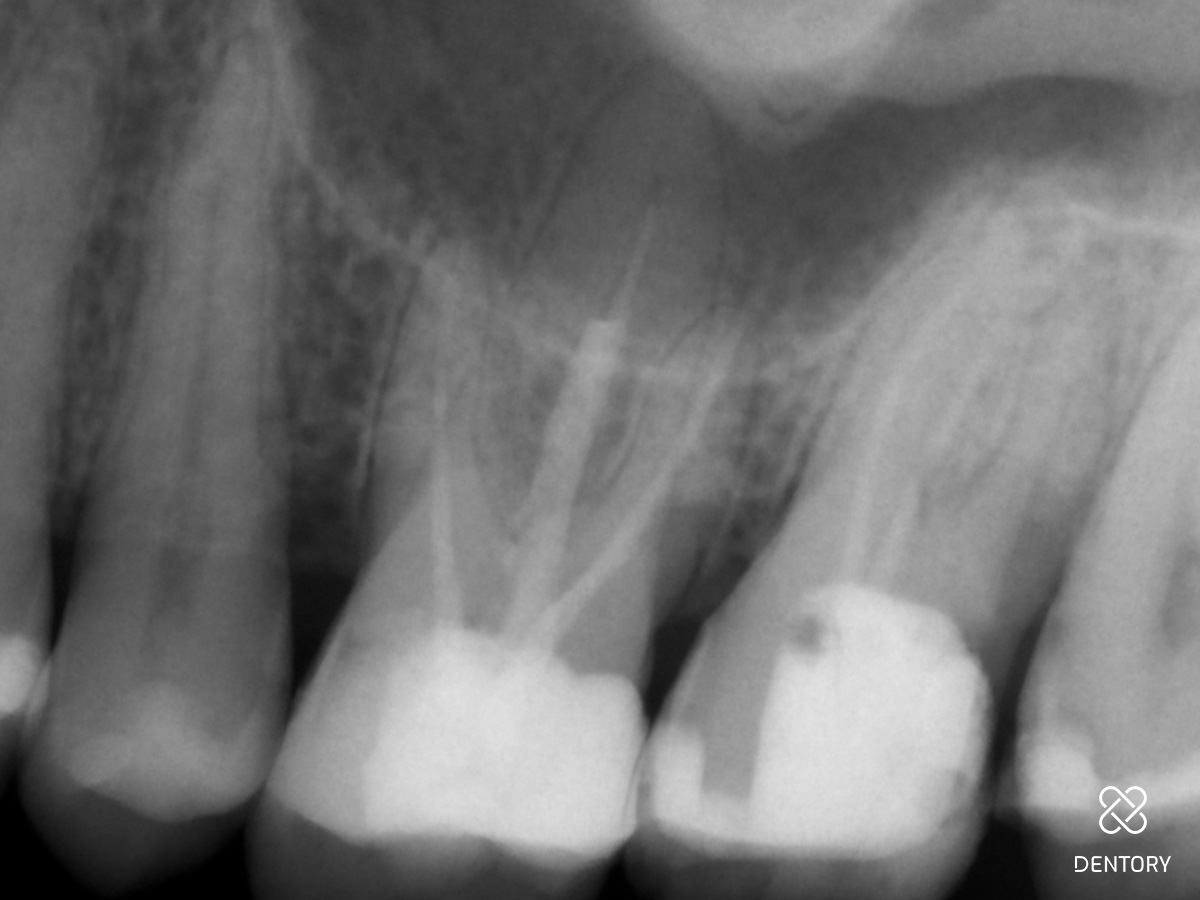

Abbildung 2

Röntgenologische Ausgangssituation.